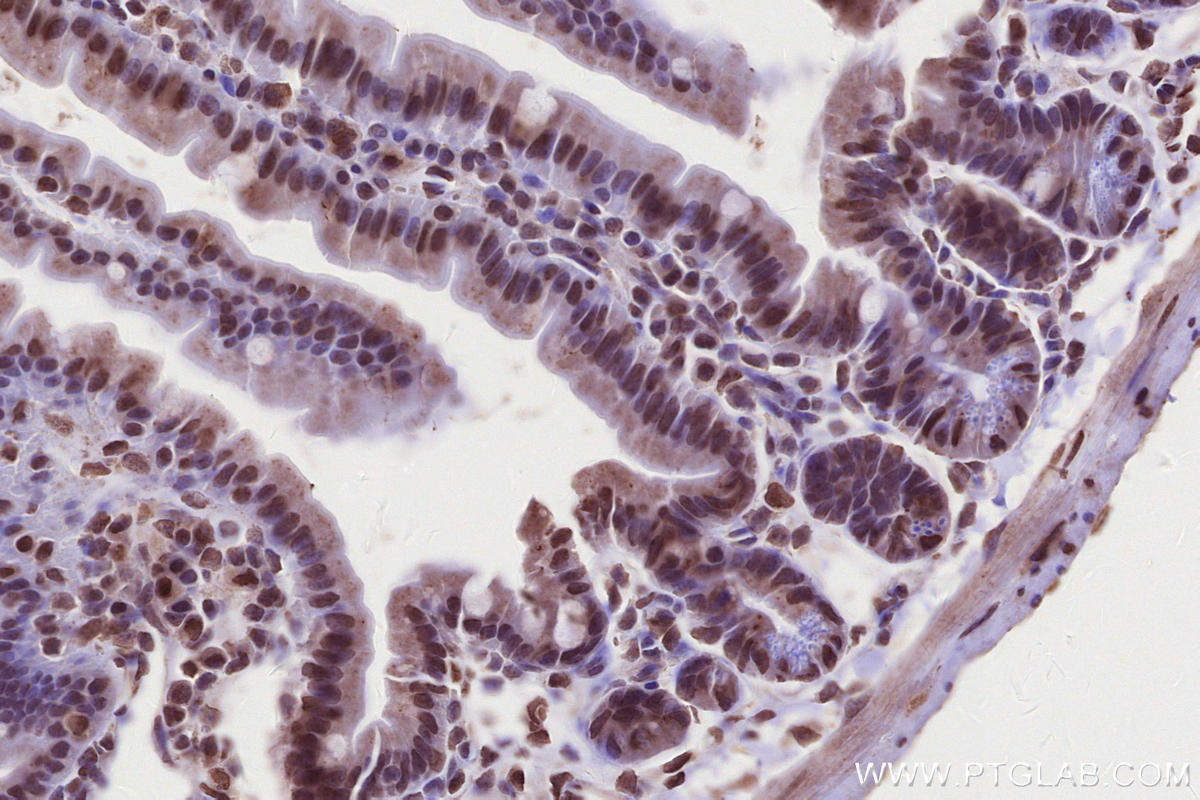

Validation Data Gallery